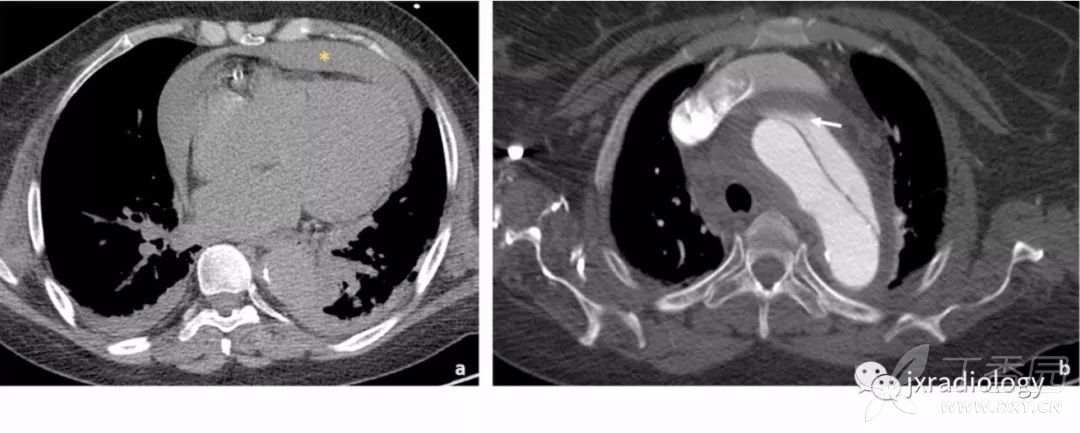

Stanford A型主动脉夹层患者出现急性心包积液时提示高死亡率,与心包填塞有关( 图16 )。

图16:平扫CT显示自发性高密度心包积液,符合心包积血(a图星号)。双侧胸腔积液可见。增强后示Stanford A型主动脉夹层,并出现假腔的局部血栓形成(b图箭头)。